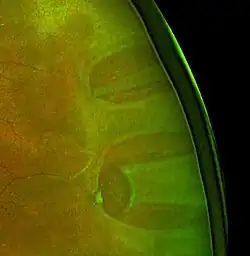

Desprendimiento de retina fotografiado a través de una lámpara de hendidura. | ||